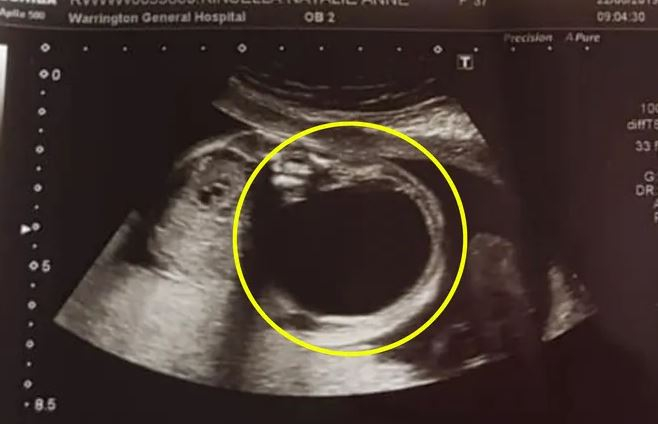

Пять месяцев беременности 38-летней англичанки Натали Кинселлы прошли без проблем. Но скрининг на 20 неделе обнаружил у плода серьезную патологию почки, которая могла привести к его гибели. Гидронефроз левой почки -  это заболевание, при котором еще толком неразвившийся орган ребенка отекает и не может выводить мочу, и она скапливается в лоханке.

Ситуацию осложняла огромная киста, которая давила на спину и другие внутренние органы плода. В больнице Натали предложили операцию, но предупредили, что хирургическое вмешательство несет риск ранних родов и замирания беременности. Оставить все как есть тоже было нельзя – киста таких размеров могла привести к смерти малыша.

Посоветовавшись с мужем, Натали решилась на операцию. На 27 неделе беременности врачи откачали шесть полных шприцов жидкости из кисты, и состояние плода улучшилось. Но неделю спустя на УЗИ обнаружилось, что киста выросла вновь – в этот раз до размеров апельсина.

Натали была раздавлена, но сохранила веру в врачей. И когда ей снова предложили лечь под нож, сразу же согласилась. На этот раз хирурги применили инновационный метод лечения – с помощью тонкой иглы, введенной в матку, плоду установили в почку шунт, который помогал отводить из нее скопившуюся жидкость.